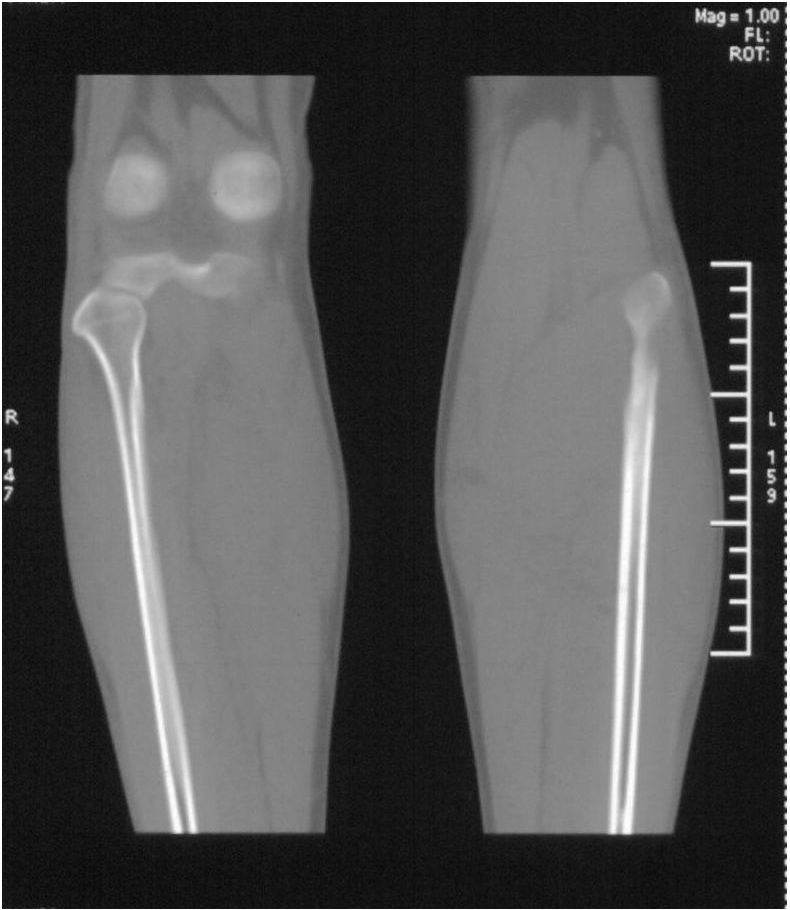

男,42岁。4个月前钢筋钝伤右侧小腿部,当时因无明显外伤,未引起重视。一周后因受伤腿部疼痛,发现肿胀,随后到当地医院进行检查(2008年4月16日)。因未发现骨质异常未引起重视,仅仅进行口服抗生素治疗处理。经过一段时间治疗但未见明显治疗效果在5月29日又进行x线检查,发现有胫骨密度上段密度增高,又进行抗炎治疗,仍未见效果。又在7月3日进行x线检查,仍然报告有胫骨上端密度增高,并建议ct检查。以下是相关检查结果:

髓腔密度呈絮状增高,胫骨上端内侧可见层状骨膜反应,考虑骨髓炎.

髓腔密度呈絮状增高,胫骨上端内侧可见层状骨膜反应,肌间隙模糊,考虑骨髓炎.

破坏、增生、骨膜反应,考虑骨髓炎